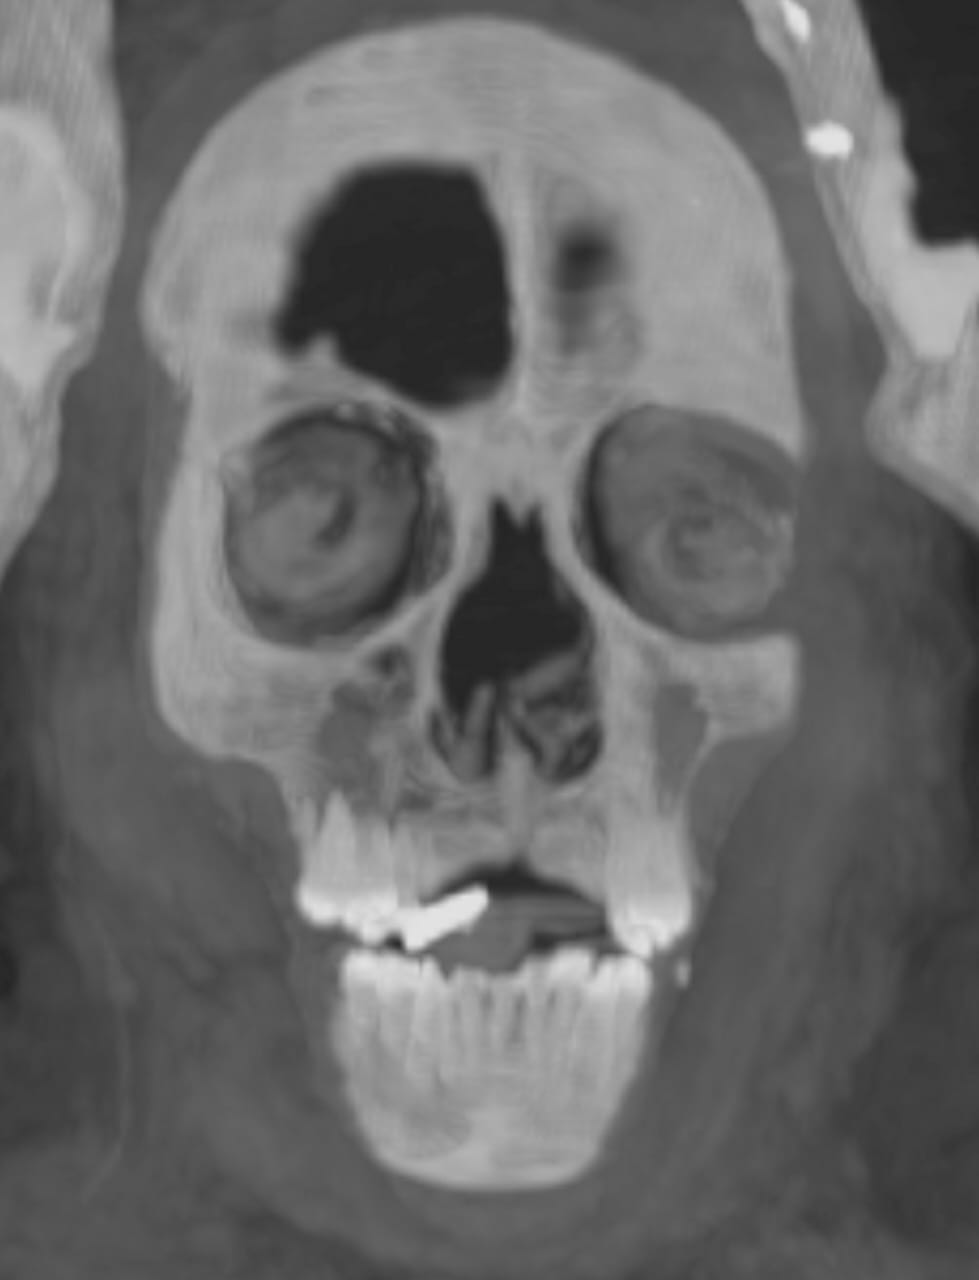

كما أوضحت صور الأشعات المقطعية الثنائية والثلاثية الأبعاد عن وجود حوالي 49 تميمة مرتبة ترتيبًا منمقًا في ثلاث أعمدة بين طيات اللفائف الكتانية وبداخل تجويف المومياء. كما أظهرت الأشعة أيضا 21 شكلًا مختلفًا للتمائم مثل عين المعبود حورس والجعران وتميمة الأفق والمشيمة وعقدة إيزيس والريشتان، وغيرهم.

ومن خلال نتائج قياسات الأشعة تبين أن 30 تميمة من التمائم المكتشفة داخل المومياء صنعت من الذهب بينما باقي التمائم صنعت من الأحجار أو الفيانس، بالإضافة إلى تميمة علي شكل لسان من الذهب وضعت بداخل فم المتوفي ليتمكن من التكلم في العالم الآخر، كما يوجد تميمة على شكل أصبعين أسفل الجذع لحماية فتحة التحنيط، وتميمة أخرى كبيرة من الذهب لجعران القلب موجودة بداخل تجويف صدر المومياء، والذي تم عمل مستنسخ منه باستخدام الطباعة ثلاثية الأبعاد.